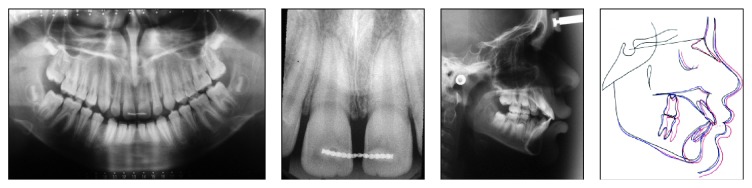

A 9-year, 5-month-old male patient came for a consultation with the chief complaint that he did not like the gap between his maxillary central incisors because it resulted in his exposure to bullying at school. On examination, the following factors were revealed: class I malocclusion, overjet of 4.0 mm, mild overbite, diastema between the central incisors of 9 mm (the mother reported that the extraction of a mesiodens was performed at the age of 8), diastemas between the central and lateral incisors and between the lower incisors, a labial frenulum with a low insertion, and rotation of the incisors (Figures 1 and 2). The correct mandibular midline was diagnosed with consideration of the maxillary midline via the “V” cupid bow technique [9] (Figure 3).

Figure 1.

Pretreatment intraoral photographs.

Figure 2.

Pretreatment radiographs.

Radiographically, the correct sequence of eruption, skeletal class I malocclusion, a sagittal growth trend, and proclination of the maxillary and mandibular incisors were noted (Figure 2).